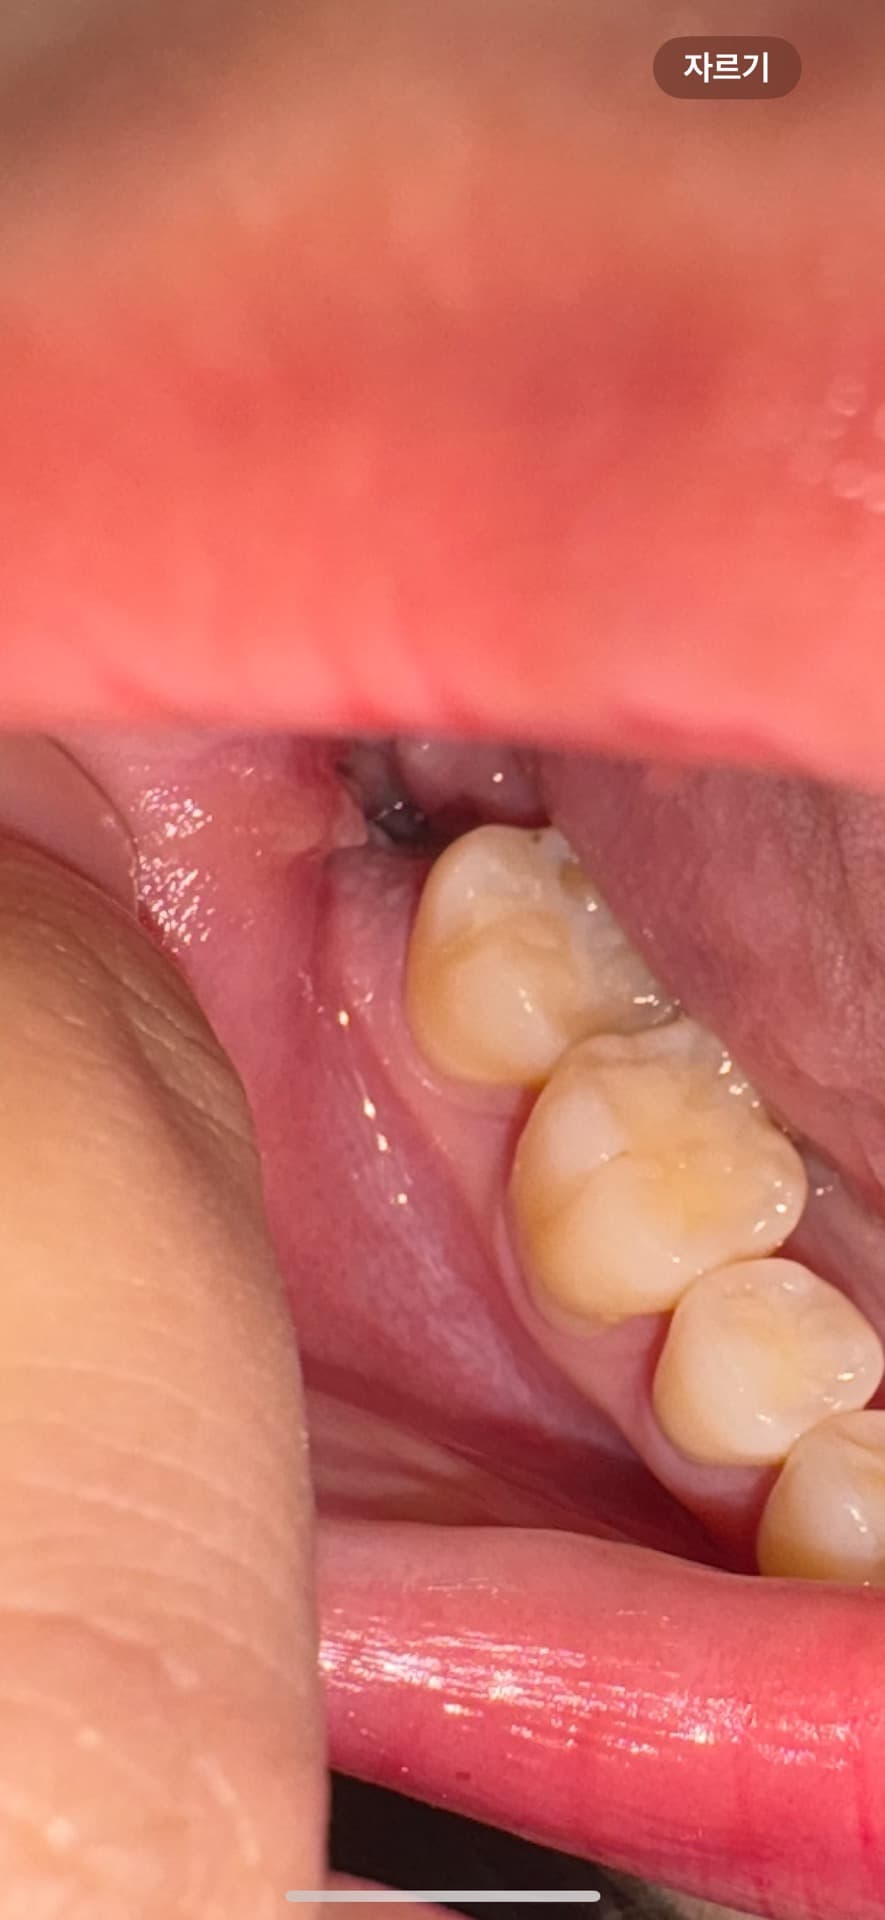

드라이소켓 가능성있을까요.. ㅜㅜ

이틀차인데 갑자기 피딱지도 안보이고 뭐가 보이지 않습니다. 혹시 피딱지가 떨어진거일까요..? 피가 나거나 아직 그러진 않은데 무섭네요

사진상으로는 발치한 공간이 잘 아물고 있습니다. 지혈만 잘되엇다면 크게 신경쓰지 않으셔도 될것같습니다.

사진을 봤을 경우에는 드라이 소켓이 아닌것으로 보입니다. 드라이 소켓이 생기면 통증이 심하고 냄새가 나는 경우가 많기 때문에 해당증상이 없다면 드라이 소켓이 아닐가능성이 높습니다.

자세한 확인을 위해서 치과에서 진료를 받아보는 것을 권유드립니다.

원래 혈병(피딱지)은 하루,이틀이면 다 흡수되어 잇몸 치유에 필요한 조직으로 바뀝니다. 너무 걱정 마세요

사진상으로는 특별히 문제가 보이진 않습니다. 드라이소켓의 경우에는 극심한 통증이 동반됩니다.